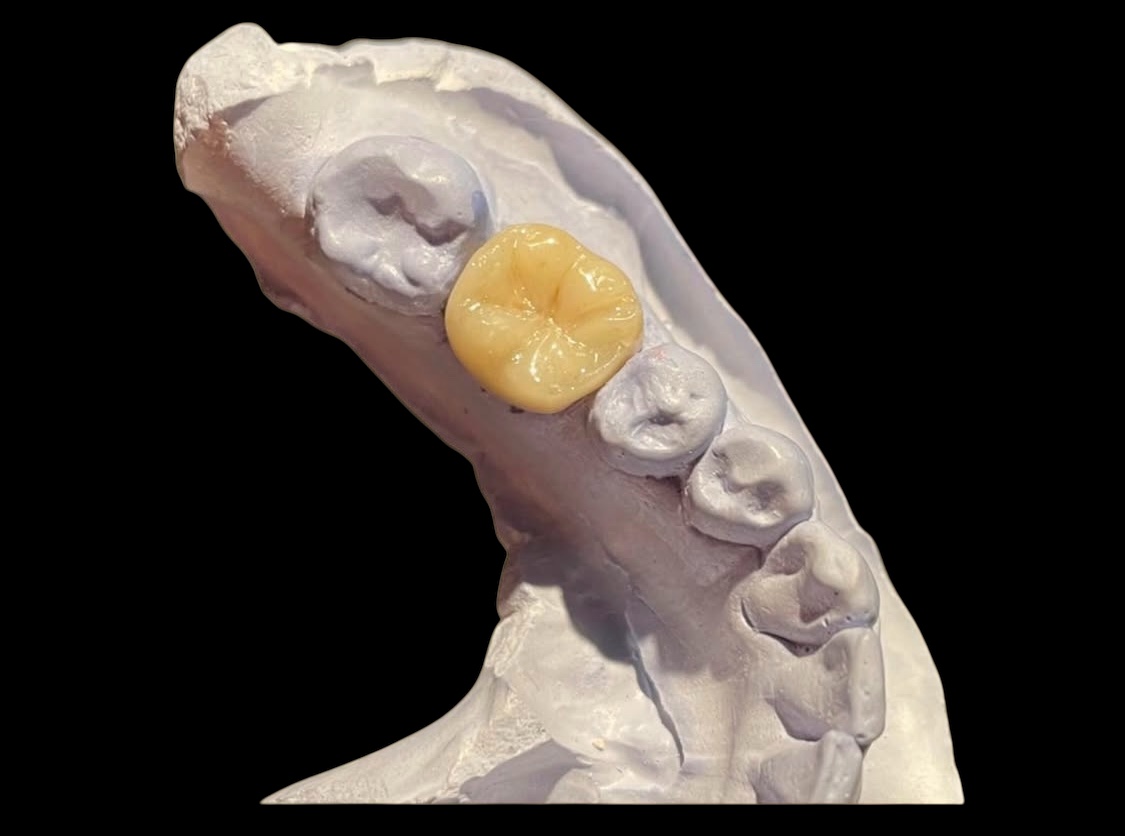

Producto 2

Descripción de ejemplo para el producto 2.